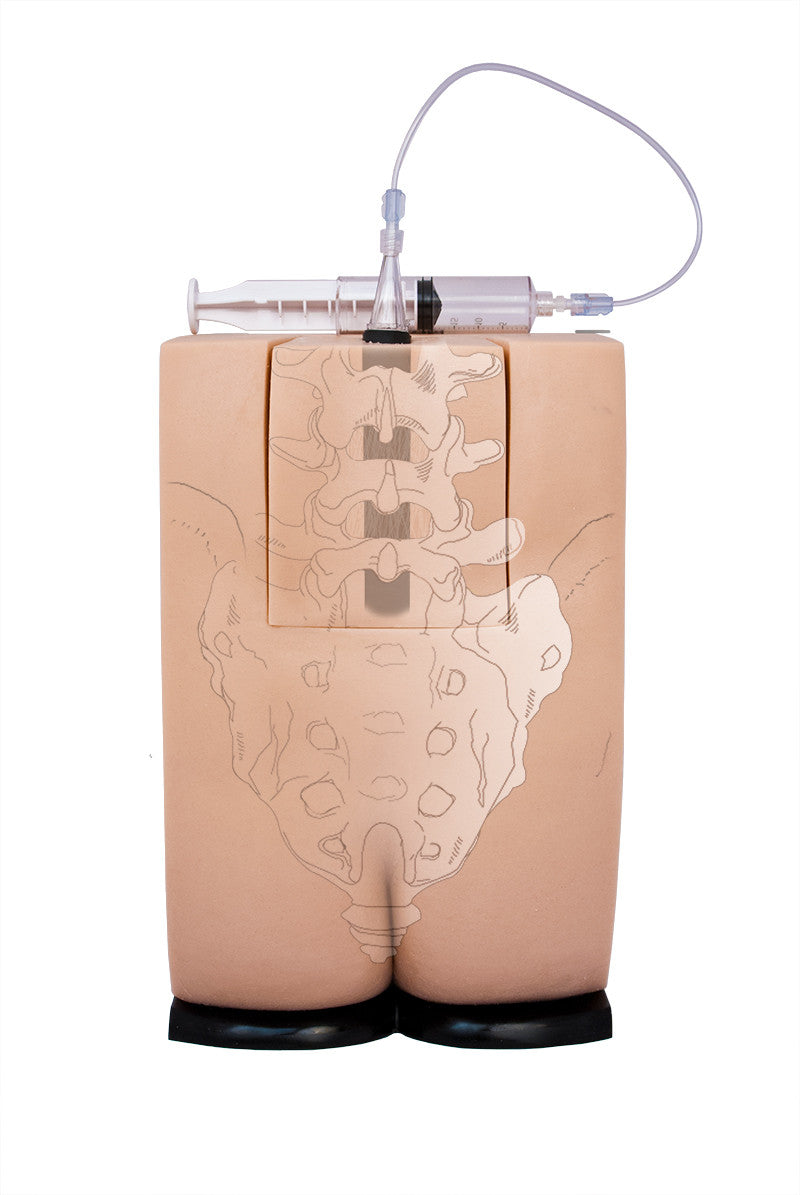

Epidural Injection Trainers

Train students and healthcare professionals in essential epidural injection skills using our highly realistic spine simulators, designed to enhance clinical training and procedural accuracy.

Our range of epidural injection trainers includes detailed anatomical models that replicate the lumbar and thoracic spine, providing a hands-on learning experience for anaesthetists, medical students, and pain management specialists. These advanced simulators allow users to practise needle placement, identify key anatomical landmarks, and develop proficiency in administering epidural and spinal anaesthesia with confidence. Ideal for medical schools, hospitals, and professional training programmes, these epidural trainers support skill development in regional anaesthesia, labour pain management, and spinal procedures. With lifelike materials that simulate real patient responses, our models offer a realistic and immersive training experience.